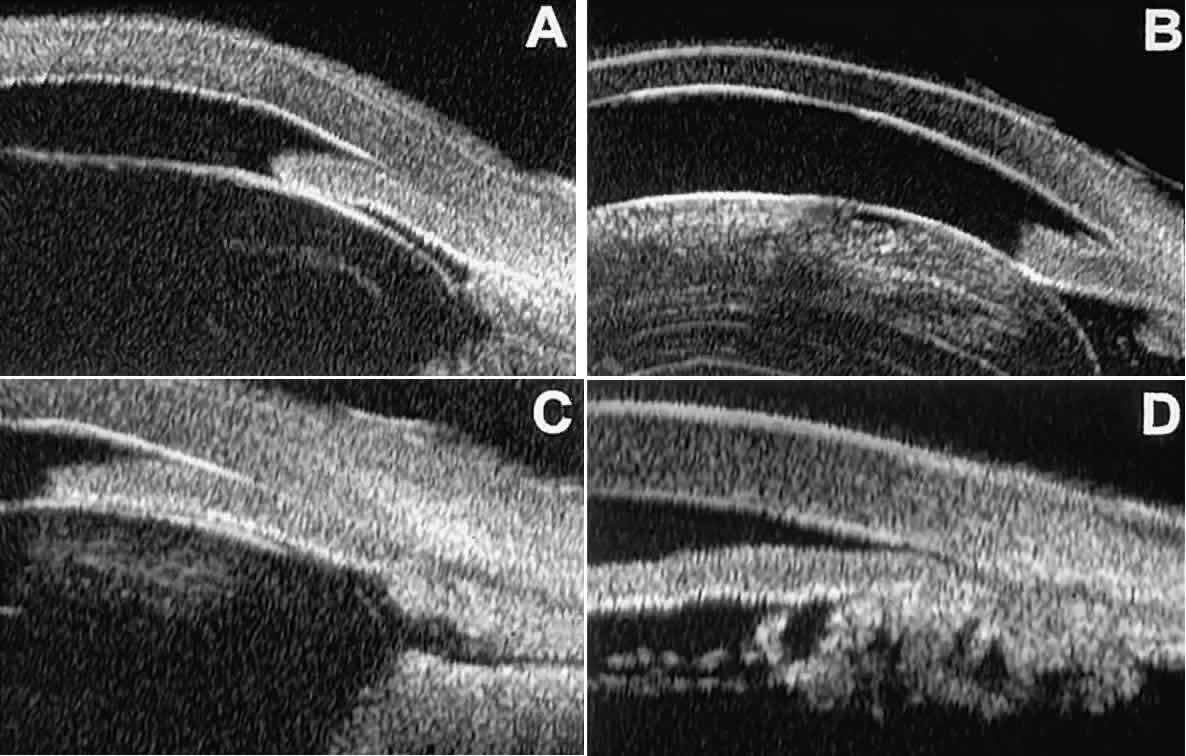

In open-angle glaucoma, UBM can be used to measure the anterior chamber angle in degrees, to assess the configuration of the peripheral iris, and to evaluate the trabecular meshwork (Fig. 9).2,4 The angle configuration can be graded and compared with gonioscopic findings. In certain patients with open-angle glaucoma, UBM can provide information that may be of some diagnostic value (Fig. 10). For example, in pigment dispersion syndrome (see Fig. 10A),6 UBM typically reveals posterior bowing of the peripheral iris (“q” configuration of peripheral iris by Spaeth classification5). In plateau iris syndrome (see Fig. 10B),7 UBM usually reveals abnormally steep anterior angulation of the peripheral iris (“s”configuration of peripheral iris by Spaeth classification5), insertion of the iris from the anterior ciliary body, and retroiridic projection of the ciliary processes. In eyes with peripheral anterior synechiae (see Fig. 10C and D), UBM can reveal the extent of iridocorneal adhesion even if the cornea is hazy or opaque.

Fig. 9. Angle configuration in eyes with open-angle glaucoma. A. Wide open angle with flat iris plane (D40r configuration by Spaeth gonioscopic grading system). B. Moderately wide angle with anteriorly bowed iris plane (C30r by Spaeth gonioscopic grading system).

Fig. 10. UBM features of special glaucoma cases. A. Pigment dispersion syndrome with posterior bowing of peripheral iris (“q” configuration by Spaeth gonioscopic grading system). B. Plateau iris syndrome with origin of iris from anterior surface of ciliary processes behind peripheral iris, slitlike narrowing of peripheral angle, and abrupt transition from steep peripheral iris to flat iris midzone. C. Broad peripheral anterior synechia with posterior bowing of nonadherent iris. D. Peripheral anterior synechia with aqueous-filled slit between site of iridocorneal adhesion and iris root after cataract extraction with implantation of posterior-chamber IOL.

In eyes with a narrow angle, UBM shows the extent of angle closure, reveals the depth of the anterior and posterior chambers, and identifies pathologic processes pushing the lens and iris forward (Fig. 11).2–4,8 UBM has been able to differentiate between primary angle closure (i.e., cases of angle closure without additional pathology responsible for the anterior lens-iris displacement [see Fig. 11A] and secondary angle closure due to processes such as lens swelling and dislocation (see Fig. 11B), massive hemorrhagic retinal detachment pushing the lens and iris anteriorly (see Fig. 11C), and multiple neuroepithelial cysts of the iridociliary sulcus (see Fig. 11D).

Fig. 11. Angle configuration in eyes with angle-closure glaucoma. A. Primary angle-closure glaucoma with anterior displacement of lens and iris. B. Angle closure secondary to swollen, cataractous lens (phakomorphic angle closure). C. Angle closure secondary to massive hemorrhagic retinal detachment; the subretinal blood is evident in the lower right corner of the photograph. D. Angle closure secondary to multiple peripheral iris cysts.